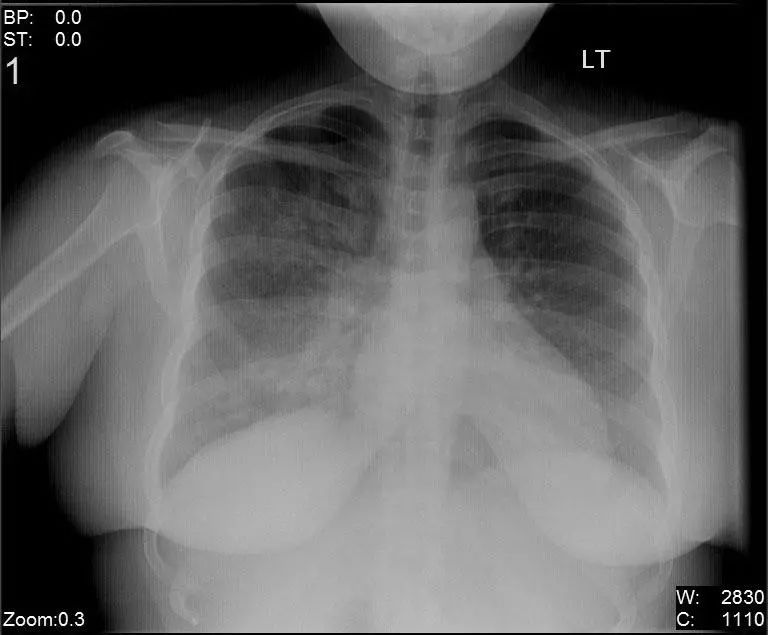

图2.4 2个月龄男孩肺炎患者,右中叶浸润,呼吸道合胞病毒(RSV)感染。